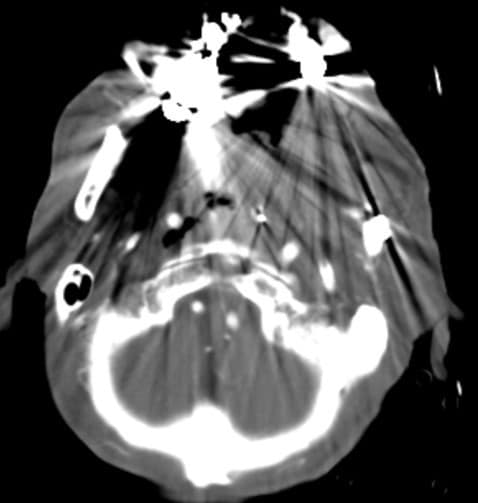

左顎下の術後部位に再発腫瘍が疑われたが、iMARなしの画像では診断が困難であった。iMARありの画像では造影剤のリークが明瞭になり、診断確定が可能になった。その後、血管塞栓術が施行され、顎動脈を選択し、コイルにて止血術が行われた。出血コントロールは良好であったが、蘇生後低酸素脳症があり、脳機能回復が見込めなかったため、12日後に死亡退院。

CT技術や撮像プロトコル設定について

本症例のような術後の場合、手術に伴う金属のメタルアーチファクトが診断の障害になることが多い。フォトンカウンティングCTではメタルアーチファクト低減アプリケーションがあり、撮影後に後処理にてメタルアーチファクトを低減することができ、撮影された画像をみて、必要に応じて、メタルアーチファクトを減らすことが可能となっている。本症例でも造影剤のリークが不明瞭であったため、メタルアーチファクトを低減することで、造影剤のリークを検出することが可能となった。